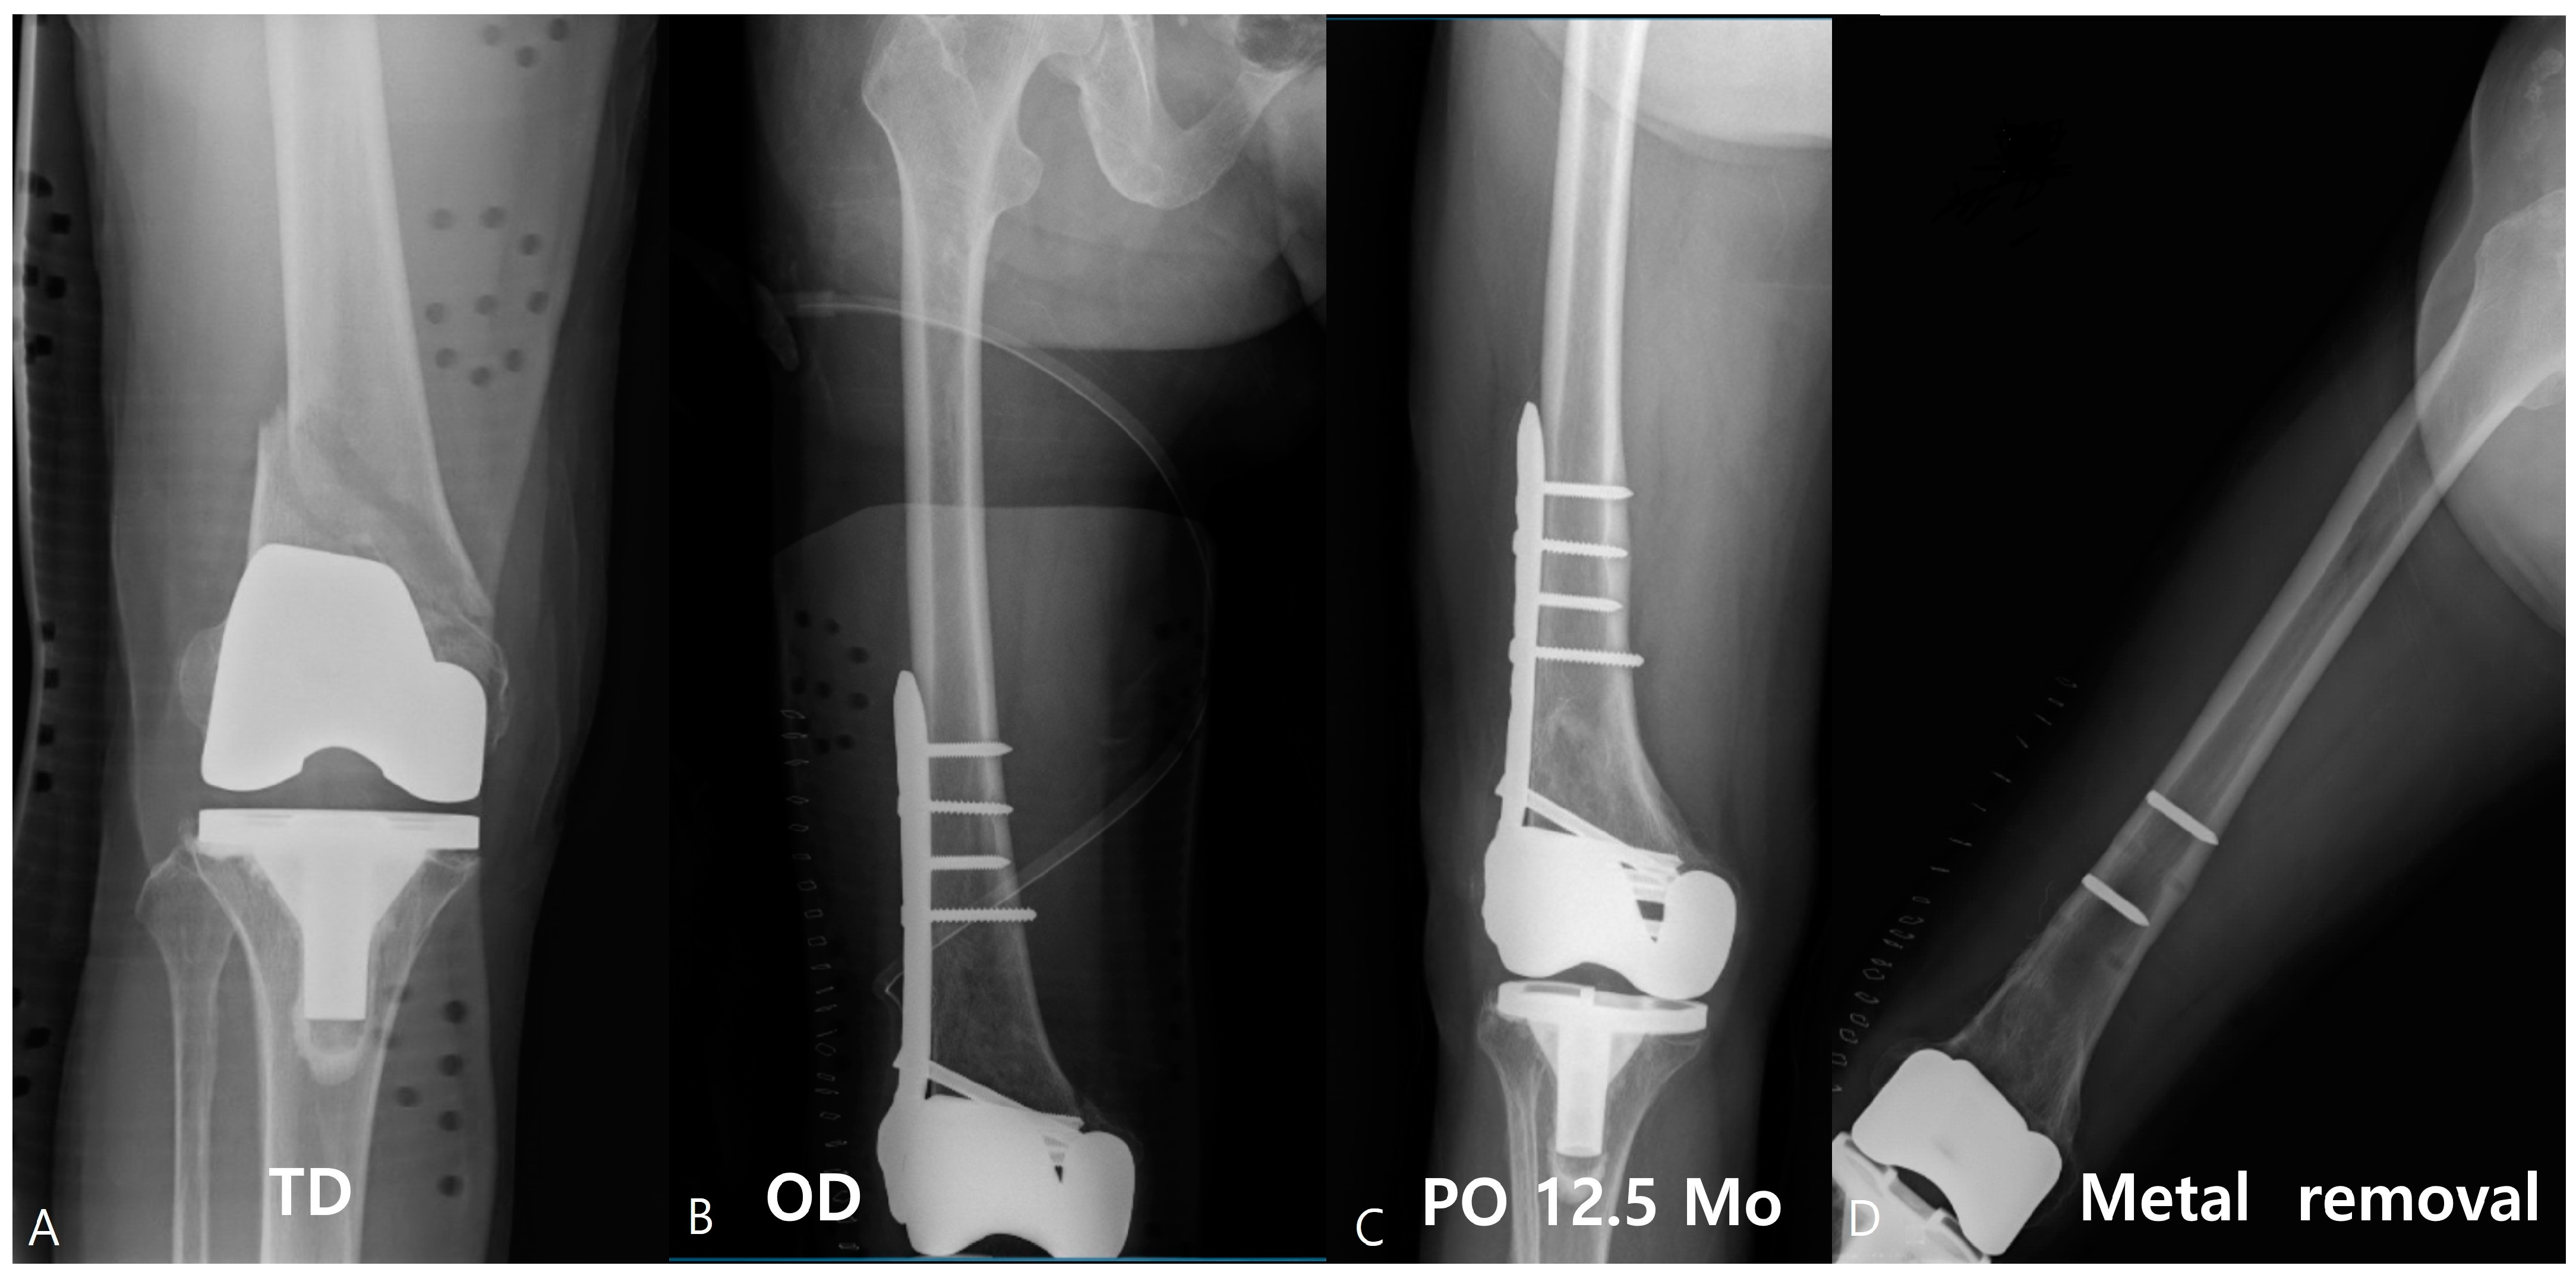

Risk Factors of Proximal Screw Breakage of Locking Plate (ZPLP®) after MIPO for Distal Femur Fractures -Analysis of Patients with Plate Removal after Bony Union-

2. Patients and Methods

2.1. Surgical Technique